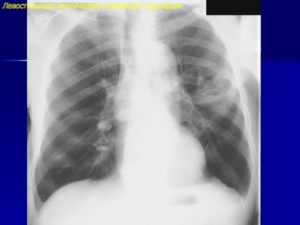

Пневмония на рентгенографии

Кроме физикальной оценки состояния больного в обязательном порядке назначаются лабораторные анализы крови и мочи, а также рентгенография, которая является отличным способом диагностики. В отдельных случаях могут понадобиться дополнительные анализы.

- Рентген в подавляющем большинстве случаев является достоверным диагностическим методом, позволяющим диагностировать воспаление легких, определить его вид, размер и локацию инфекционного очага. На снимке в апикальной части доли левого легкого заметен диффузный усиленный легочный рисунок.

Обратите внимание. При установлении диагноза врач должен исключить бронхит, астму, туберкулез и рак легких, поскольку симптоматика перечисленных заболеваний схожа.